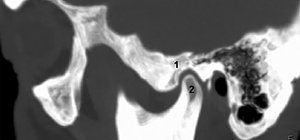

FIG 2 Coronal CT; 1: fossa, 2: condyle.

Computerized Tomography: CT examination of the TMJ should demonstrate the bony cortex, the size and shape of the condyles and their position in the fossa, the joint spaces and centric relation loading zone (a dental term meaning that the condyle is most comfortable in the posterior location of the mandible when it is manipulated gently backward and upward into a retrusive position).8 (Figs. 2-3)

FIG 3 Oblique sagittal CT of TMJ.